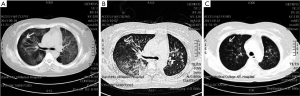

However, Crizotinib also led to some side effects, though minor ones. Although a chest CT scan showed that the tumors on the left lower lobe and hepatic had reduced significantly, along with the mediastinal lymph nodes and hilus pulmonis lymph node (Figure 3B,C), the patient experienced a low-grade fever, chest tightness, shortness of breath and Karnofsky performance status (KPS) (7) rating falling to 60 point. The lung exudative lesions had increased in size (Figure 4A). Considering the symptoms like wet rales and shortness of breath, the history of Crizotinib administration, imaging findings and lack of bacterial growth found on multiple sputum cultures, a diagnosis of Crizotinib-induced level 4 interstitial pneumonia (Common Terminology Criteria for Adverse Events, v.3.0) was performed. The patient was therefore administered with dexamethasone 10 mg plus cefuroxime 2.0 mg twice a day and oxygen inhalation. Quick medical follow-up and treatment could reduce the chest tightness and shortness of breath. Significantly, a rise on KPS score was witnessed, whereby improving the symptoms. CT scan showed that the pulmonary exudative lesion area disappeared in contrast with the results of the previous scan lesion area (Figure 4B,C). Finally, on October 14, 2013, the patient was discharged from the hospital accounting for the signs of recovery. And continuous treatment with lower dosages was still needed.